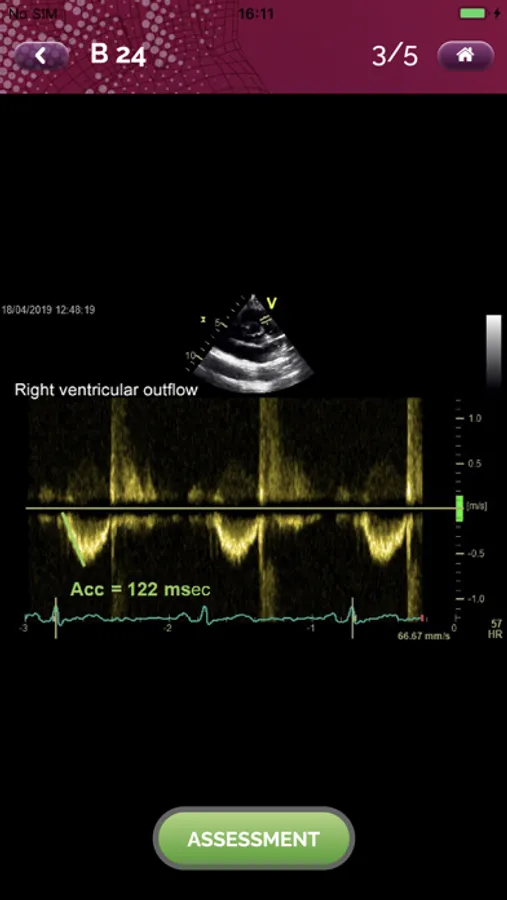

EchoRight Pro Screenshots